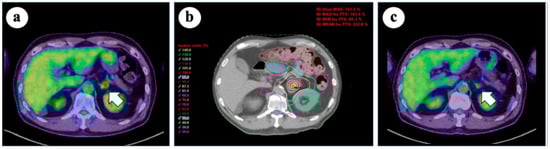

5. Adrenal Oligometastases of Lung Cancer